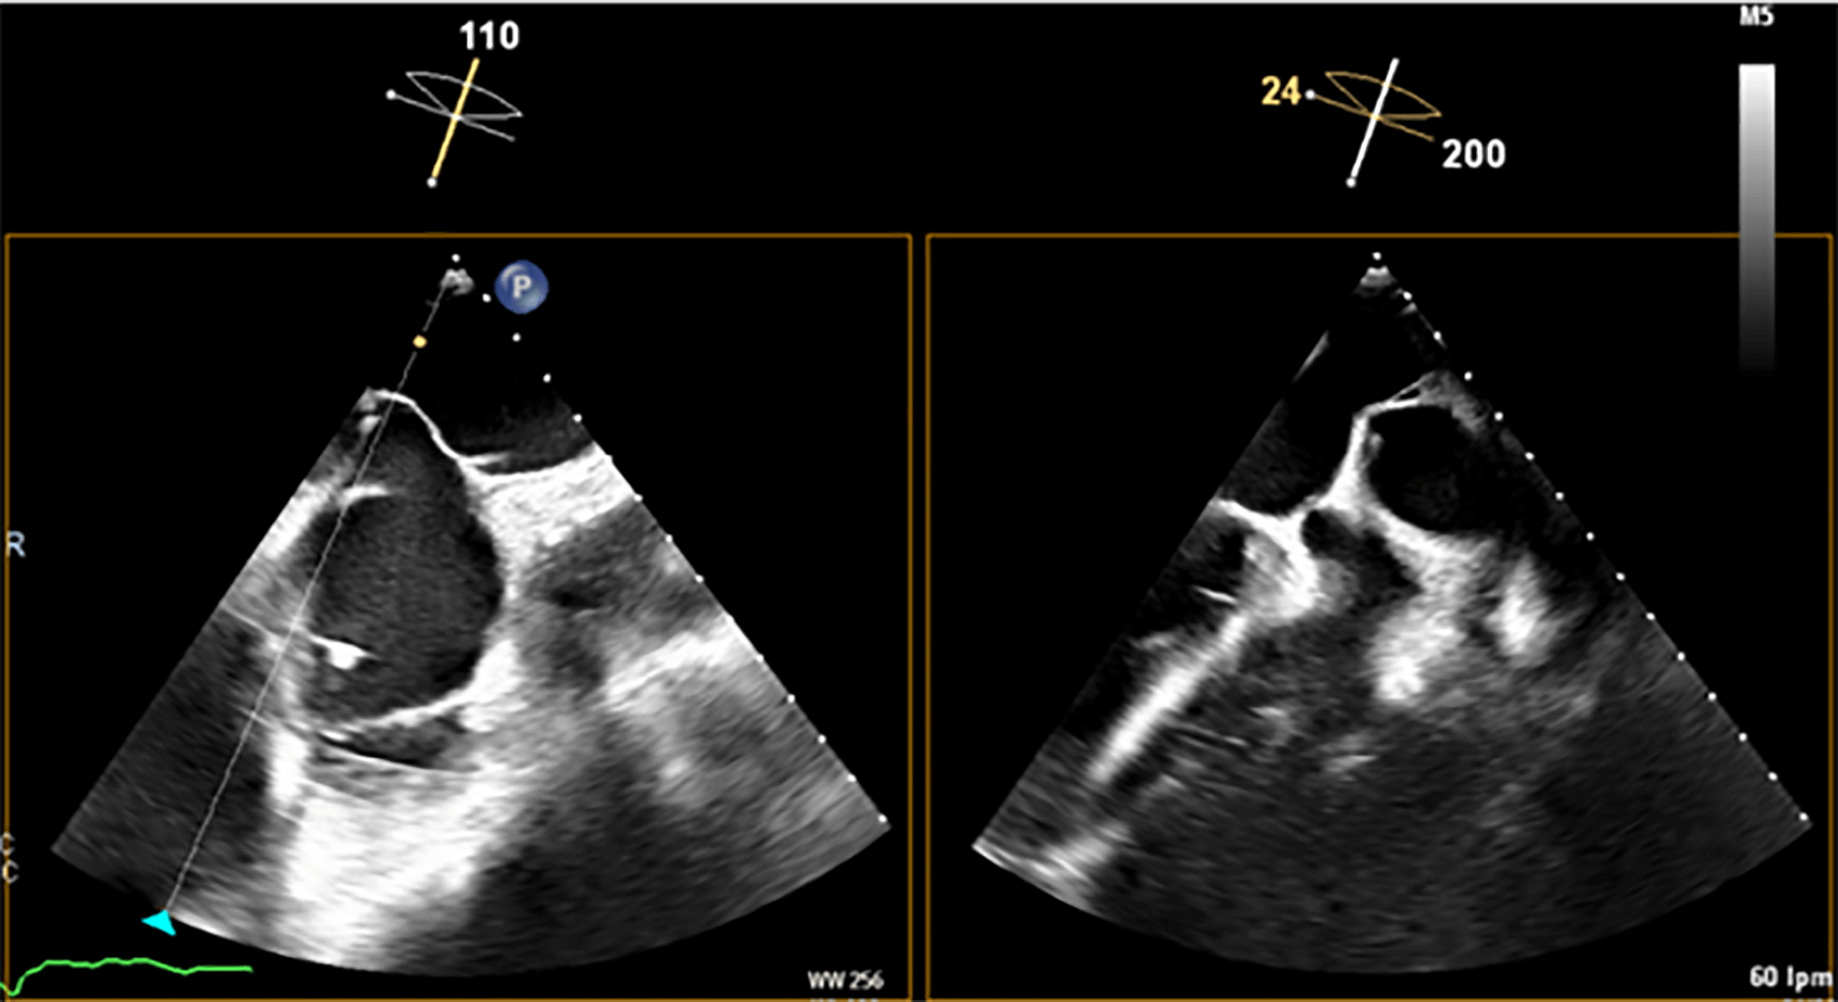

Fig. 4.

Left atrial appendage closure (LAAC) in a patient with complex anatomy. Transesophageal echocardiography (TEE) revealed a left atrial appendage (LAA) with a large proximal lobe, presenting a challenge for percutaneous closure. Nevertheless, an Amulet device was deployed successfully, with the lobe of the device positioned in the proximal lobe of the LAA and the disc effectively sealing the anatomical ostium.